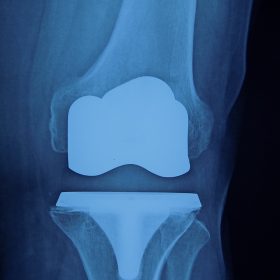

Σε αυτό το σημείο η Αρθροπλαστική Γονάτου αποτελεί μονόδρομο.